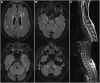

Despite the growing evidence supporting the existence of CNS involvement in acute and chronic graft-versus-host disease (CNS-GvHD), the characteristics and course of the disease are still largely unknown. In this multicentre retrospective study, we analysed the clinical, biological, radiological and histopathological characteristics, as well as the clinical course of 66 patients diagnosed with possible CNS-GvHD (pCNS-GvHD), selected by predetermined diagnostic criteria. Results were then contrasted depending on whether pCNS-GvHD onset occurred before or after Day 100 following allogeneic haematopoietic stem cell transplantation (allo-HSCT). The median time between allo-HSCT and pCNS-GvHD onset was 149 days (interquartile range25-75 48-321), and pCNS-GvHD onset occurred before Day 100 following transplantation in 44% of patients. The most frequent findings at presentation were cognitive impairment (41%), paresis (21%), altered consciousness (20%), sensory impairment (18%) and headache (15%). Clinical presentation did not significantly differ between patients with pCNS-GvHD occurring before or after Day 100 following transplantation. Brain MRI found abnormalities compatible with the clinical picture in 57% of patients, while CT detected abnormalities in only 7%. Seven patients had documented spinal cord MRI abnormalities, all of them with pCNS-GvHD occurring after Day 100 following transplantation. In the CSF, the white blood cell count was increased in 56% of the population (median 18 cells/μl). Histopathological analyses were performed on 12 specimens and were suggestive of pCNS-GvHD in 10. All compatible specimens showed parenchymal and perivascular infiltration by CD3+ and CD163+ cells. Immunosuppressive therapy was prescribed in 97% of patients, achieving complete clinical response in 27%, partial improvement in 47% and stable disease in 6%. Response to immunosuppressive therapy did not differ significantly between patients with pCNS-GvHD occurring before or after Day 100 following transplantation. Clinical relapse was observed in 31% of patients who initially responded to treatment. One-year overall survival following pCNS-GvHD onset was 41%. Onset before Day 100 following haematopoietic stem cell transplantation [hazard ratio with 95% confidence interval: 2.1 (1.0-4.5); P = 0.041] and altered consciousness at initial presentation [3.0 (1.3-6.7); P = 0.0077] were associated with a reduced 1-year overall survival probability. Among surviving patients, 61% had neurological sequelae. This study supports that immune-mediated CNS manifestations may occur following allo-HSCT. These can be associated with both acute and chronic GvHD and carry a grim prognosis. The clinical presentation as well as the radiological and biological findings appear variable.